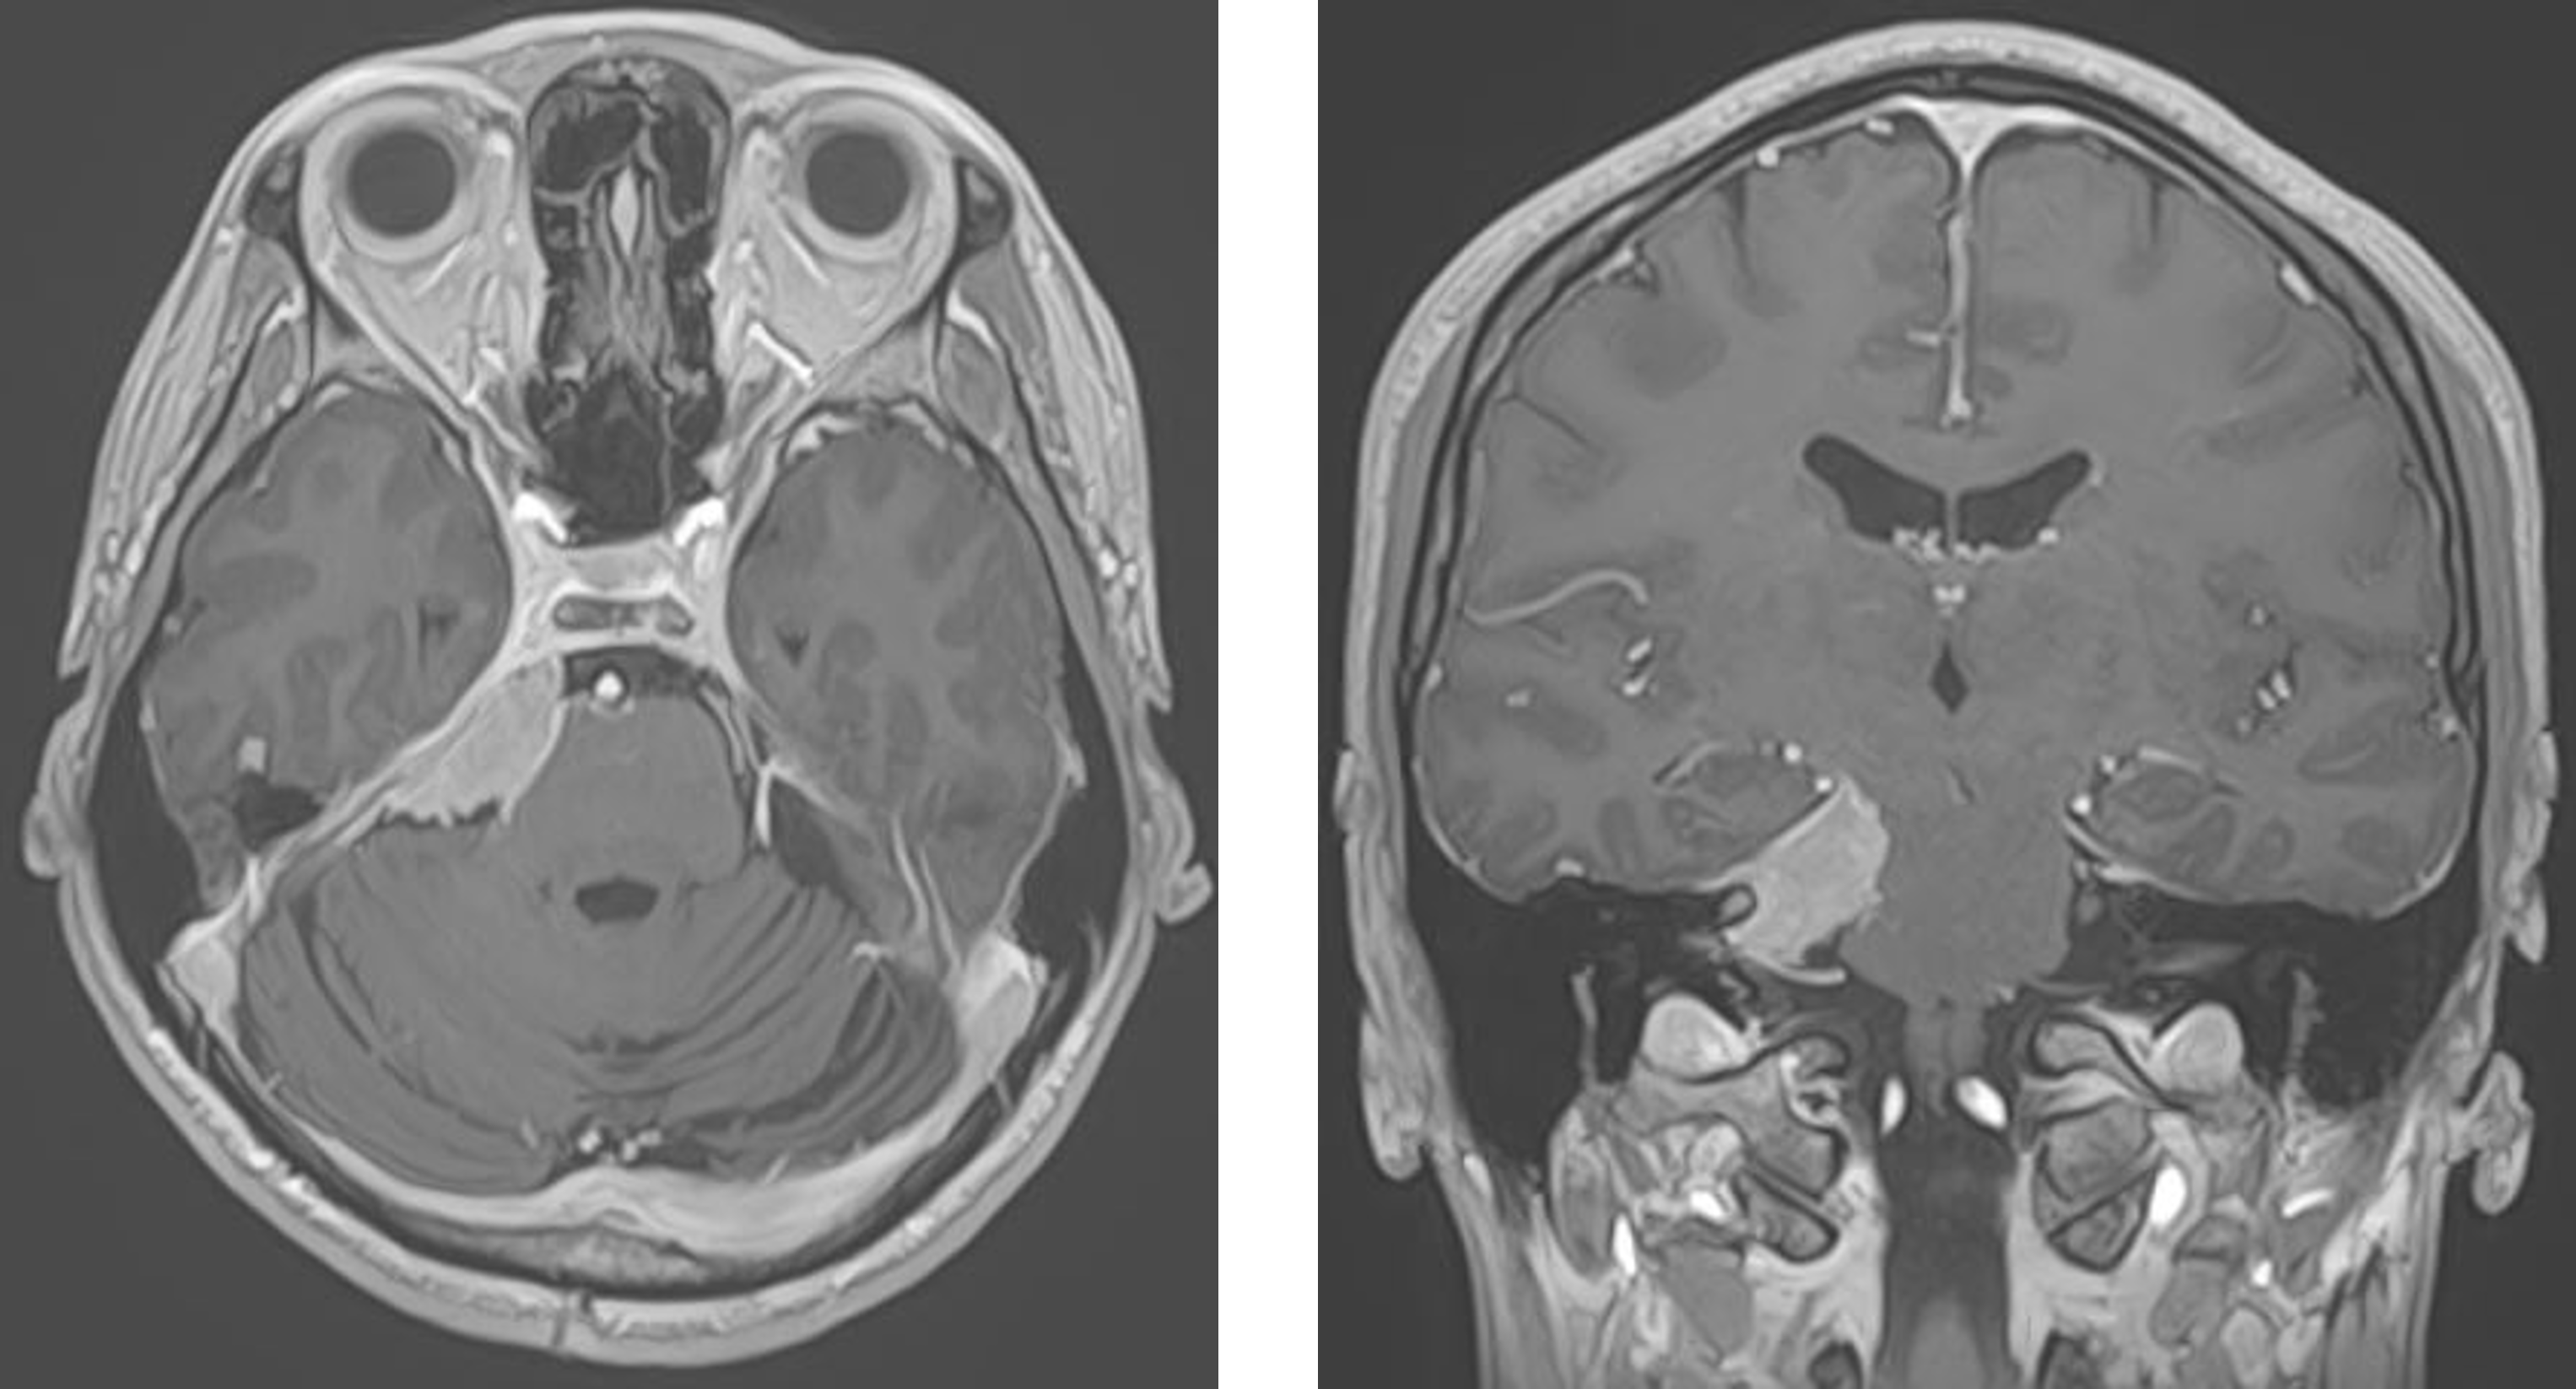

髄膜腫は原発性脳腫瘍のうち最も頻度の高いものです。緩徐な増大を来し無症状であることも多く、脳ドック検査などで偶然発見される場合もあります。治療後も再発や転移を起こさない良性の経過を来すものが多いですが、一部に細胞分裂が速かったり、何度も再発を来すような悪性度の高いものが存在しますので注意が必要です。小さく進行がゆっくりであるものは経過観察を行うことが一般的です。摘出の難易度を左右する要因は、腫瘍の部位、大きさ、硬さ、栄養血管の豊富さなどがあげられます。腫瘍が大きい場合は、周囲の脳や神経、正常血管と癒着している場合があります。頭蓋内の深部に存在するものは手術の難易度が高い場合があります。手術は血流が多い症例もあり、術前に血管内治療で栄養血管を塞栓した方が手術時の出血量を減らせたりすることが多く、この方法を取り入れています。

頭蓋底腫瘍は頭蓋骨の底部に発生する腫瘍の総称です。腫瘍が脳の深部にあること、 また多くの重要な神経組織や血管などが近くにあるため、危険性が高く、治療成績は思わしくありませんでした。しかし近年では、顕微鏡に加えて内視鏡を用いた手術手技が開発され、手術成績はかなり向上してきています。当院では、手術の部位により、外視鏡と顕微鏡を組み合わせた手術手技を行っております。低侵襲で、かつ最大限の摘出を目的とする取り組みを行っております。下垂体を含むトルコ鞍近傍に発生する腫瘍が多いですが、中頭蓋窩、後頭蓋窩に発生する腫瘍性病変に対しても良好な治療成績を得ております。